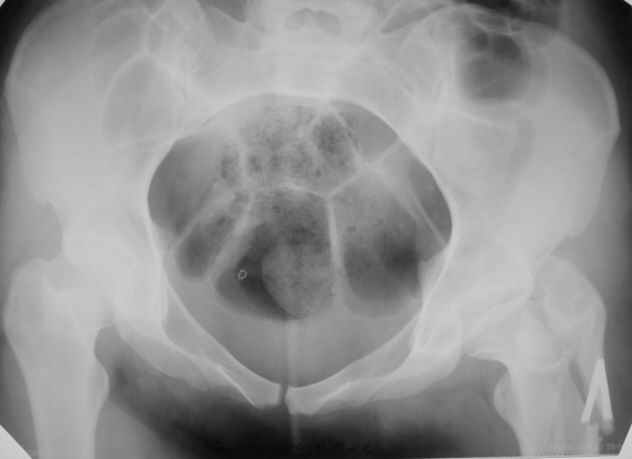

Пациентка 23 лет, доставлена в клинику с Диагнозом: Закрытый сегментарный оскольчатый перелом левой бедренной кости в верхней и средней трети. Травма в результате ДТП 10.03.2006г. Из анамнеза у пациентки диспластический левосторонний коксартроз, S-образный сколиоз 2ст. В 1999г в Кургане выполнялась остеотомия бедра в нижней трети и коррекция укорочения конечности на 3 см (рентгенограммы бедра и таза до травмы в приложении). До получения травмы пациентка ходила без боли с полной нагрузкой на левую ногу. Учитывая дисплазию левого ТБС, пациентке, вероятно, предстоит операция тотального эндопротезирования лев ТБС, что требует анатомичного восстановления проксимальногоотдела бедра. Рассматриваются следующие вариант остеосинтеза:1) Экстракортикальный остеосинтез проксимального и дистального перелома пластиной с угловой стабильностью типа LISS( г Рыбинск); 2) Ретроградный интрамедуллярный блокированный остеосинтез дистального перелома и накостный синтез проксимального пластиной с угловойстабильностью; 3) Остеосинтез бедра в аппарате внешней фиксации с фиксацией таза и возможной открытой адаптацией фрагментов. Хотелось бы узнать Ваше мнение. С уважением Украинский Евгений, г.Краснодар, ККБ N1, ТОО N3.

Судя по снимкам до перелома, большой вертел располагался высоковато. Может, подумать о том, чтобы при остеосинтезе его переместить дистальнее и/или латеральнее? Что скажут коллеги, активно занимающиеся эндопротезированием?